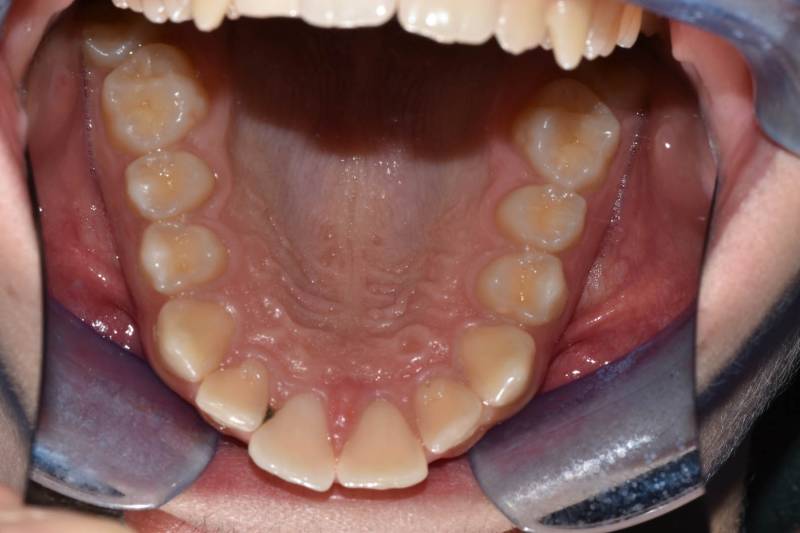

Paziente trattato con ortodonzia fissa bimascellare per 20 mesi.